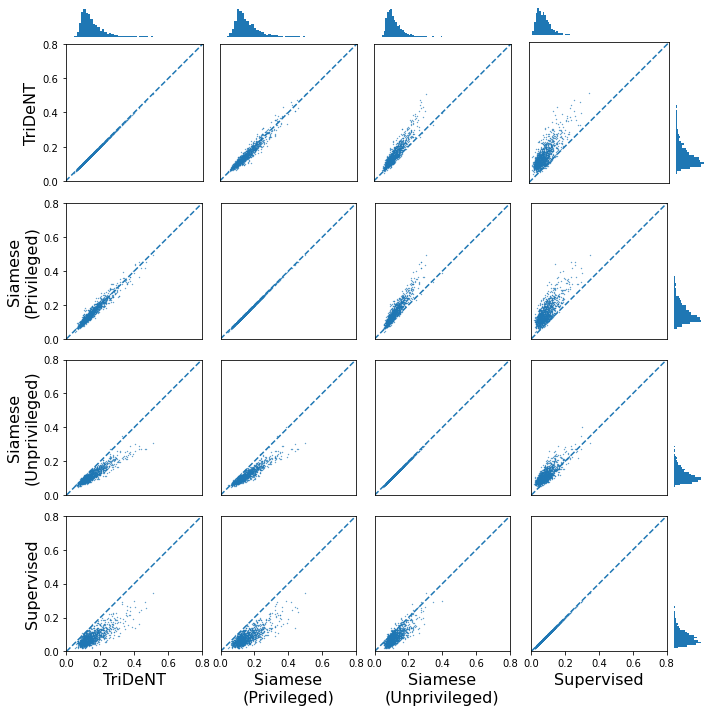

To assess the level of information shared between the transcriptomic results and the representations of the H&E patches, we investigate the cross-correlation between elements of the representations and the gene counts for each matching patch. We calculate the cross-correlation across the validation set between each element in the representations and the count for each gene, and for each gene take the correlation of the corresponding element with the maximum correlation or minimum anti-correlation, whichever has the greater absolute value. This maximum/minimum is chosen because the vast majority of elements will not correlate with any given gene, and the absolute value is taken because the sign of the element is arbitrary, so correlation and anti-correlation are equivalent. We use the absolute value of the correlation for the element selected for each gene, and use these to generate the histograms in Figure 3(a). It is clear that privileged training obtains representations which are far more correlated to the gene counts than unprivileged training, with minimal differences in the correlations between TriDeNT ♆ and Siamese approaches. This implies that the models have learned equivalently informative representations about the coarse-grained features of the genes. Figure 3(c) demonstrates that the correlation strength is significantly greater for TriDeNT ♆ compared to an unprivileged Siamese model, and Figures S3 and S4 show the relationships between the gene correlations of representations from TriDeNT ♆, Siamese methods, and supervised learning. Figures S5 and S6 show the geneset enrichment for each method, demonstrating that TriDeNT ♆ captures more meaninful interrelationships that are more informative about the relationship between tissue morphology and gene expression than unsupervised Siamese models. This is especially important for scientific discovery, as these analyses are used to generate hypotheses for further research. Figure S7 shows UMAP projections of the representation space coloured by genotype and gene, to illustrate that TriDeNT ♆ identifies distinct morphological clusters which are not found by unprivileged Siamese models. Figure 3(a) also shows that the findings are robust to human and mouse datasets, indicating the generality of the method.

To further analyse the learned representations, we produce UMAP projections of the latent space labelled with the tissue types for the NCT tissue type classification task, as shown for CD3CD20 and SMA in Figure 4(a), and for all SegPath stains in Figures S8 and S9. These figures make the reasons for the varying performance of the privileged Siamese model more apparent. For stains with better performing privileged Siamese models, such as SMA, the UMAPs are very similar between Siamese methods and TriDeNT, with well-differentiated tissue type clusters. In those with worse performance, such as ERG, the tissue types are poorly differentiated, often with only adipose and background forming distinct clusters from the other classes. On closer inspection, it is notable in these projections that TriDeNT ♆ produces more well-defined and separated clusters in general than Siamese networks. This is further evidenced in Figure S7, where TriDeNT ♆ is shown to identify clusters with overexpression of a given gene significantly more effectively than an unprivileged Siamese model.